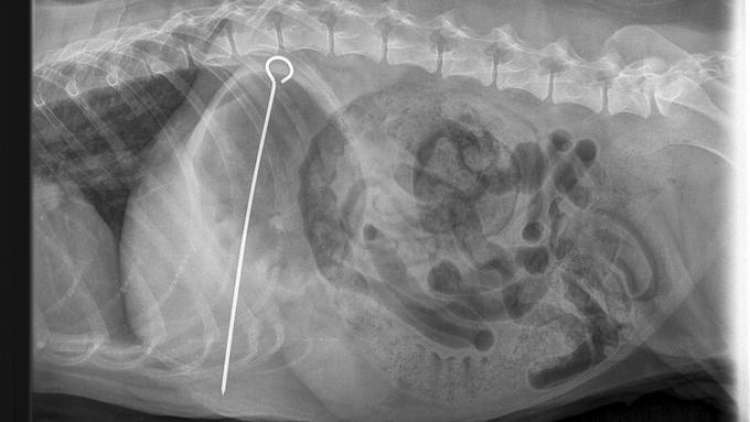

Veterinarios retiran un pincho de ocho pulgadas de un perro luego de tragárselo junto con un kebab

Los veterinarios han realizado una cirugía que salvó la vida de un perro que se tragó un pincho de metal de ocho pulgadas junto con un kebab de pollo. ...